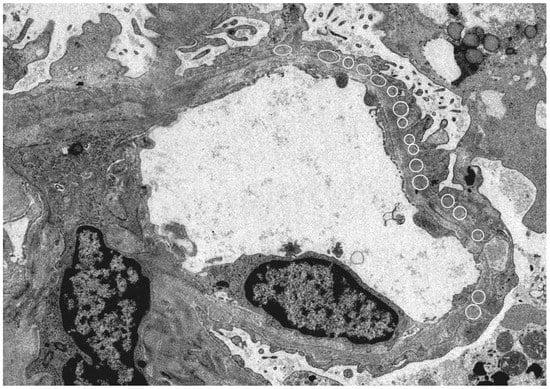

Since HBe antigen incurs a positive electric charge, and the immunoglobulin G (IgG) immune complex has a low molecular weight, immune deposition occurs under the glomerular epithelium and has a negative electric charge when passing through the basement membrane (our case; Figure 1).

Figure 1.

Electron microscope: Kidney histology of a patient with hepatitis B virus (HBV)-related membranous nephropathy (MN). There was irregularity of the basement membrane and a large number of granular accretions (open circle) were recognized on the basement membrane subcutaneously. (Image courtesy of Dr. Tadashi Yamamoto , Center of Biofluid Biomarker, Niigata University, Niigata, Japan).